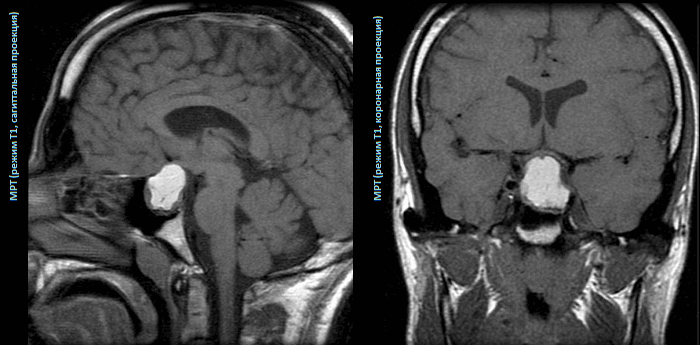

В диагностике ПА ведущую роль играют компьютерная томография (КТ) и магнитно-резонансная томография (МРТ). На КТ обнаруживают гиперденсные участки в случае острой геморрагии (в пределах 3 - 4 дней) или участки смешанной плотности - при наличии некротических тканей. САК может быть диагностировано при проникновении крови в базальные цистерны. МРТ является более чувствительным методом, определяя гиперденсные или гетерогенные участки кровоизлияний и некротические участки опухоли. Arita K. с соавт. (2001) описал утолщение слизистой клиновидного синуса, как характерную черту (в 79% случаях) острой стадии ПА (в пределах 7 дней после кровоизлияния), объясняя данный феномен нарушением венозного оттока. Анализ цереброспинальной жидкости редко оказывает помощь в диагностике ПА, поскольку при отсутствии крови в субарахноидальном пространстве ликвор обычно чистый. С другой стороны, в зависимости от времени, прошедшего от момента геморрагии, ликвор может содержать кровь или быть ксантохромным. Часто отмечается незначительный плеоцитоз и повышение уровня белка.